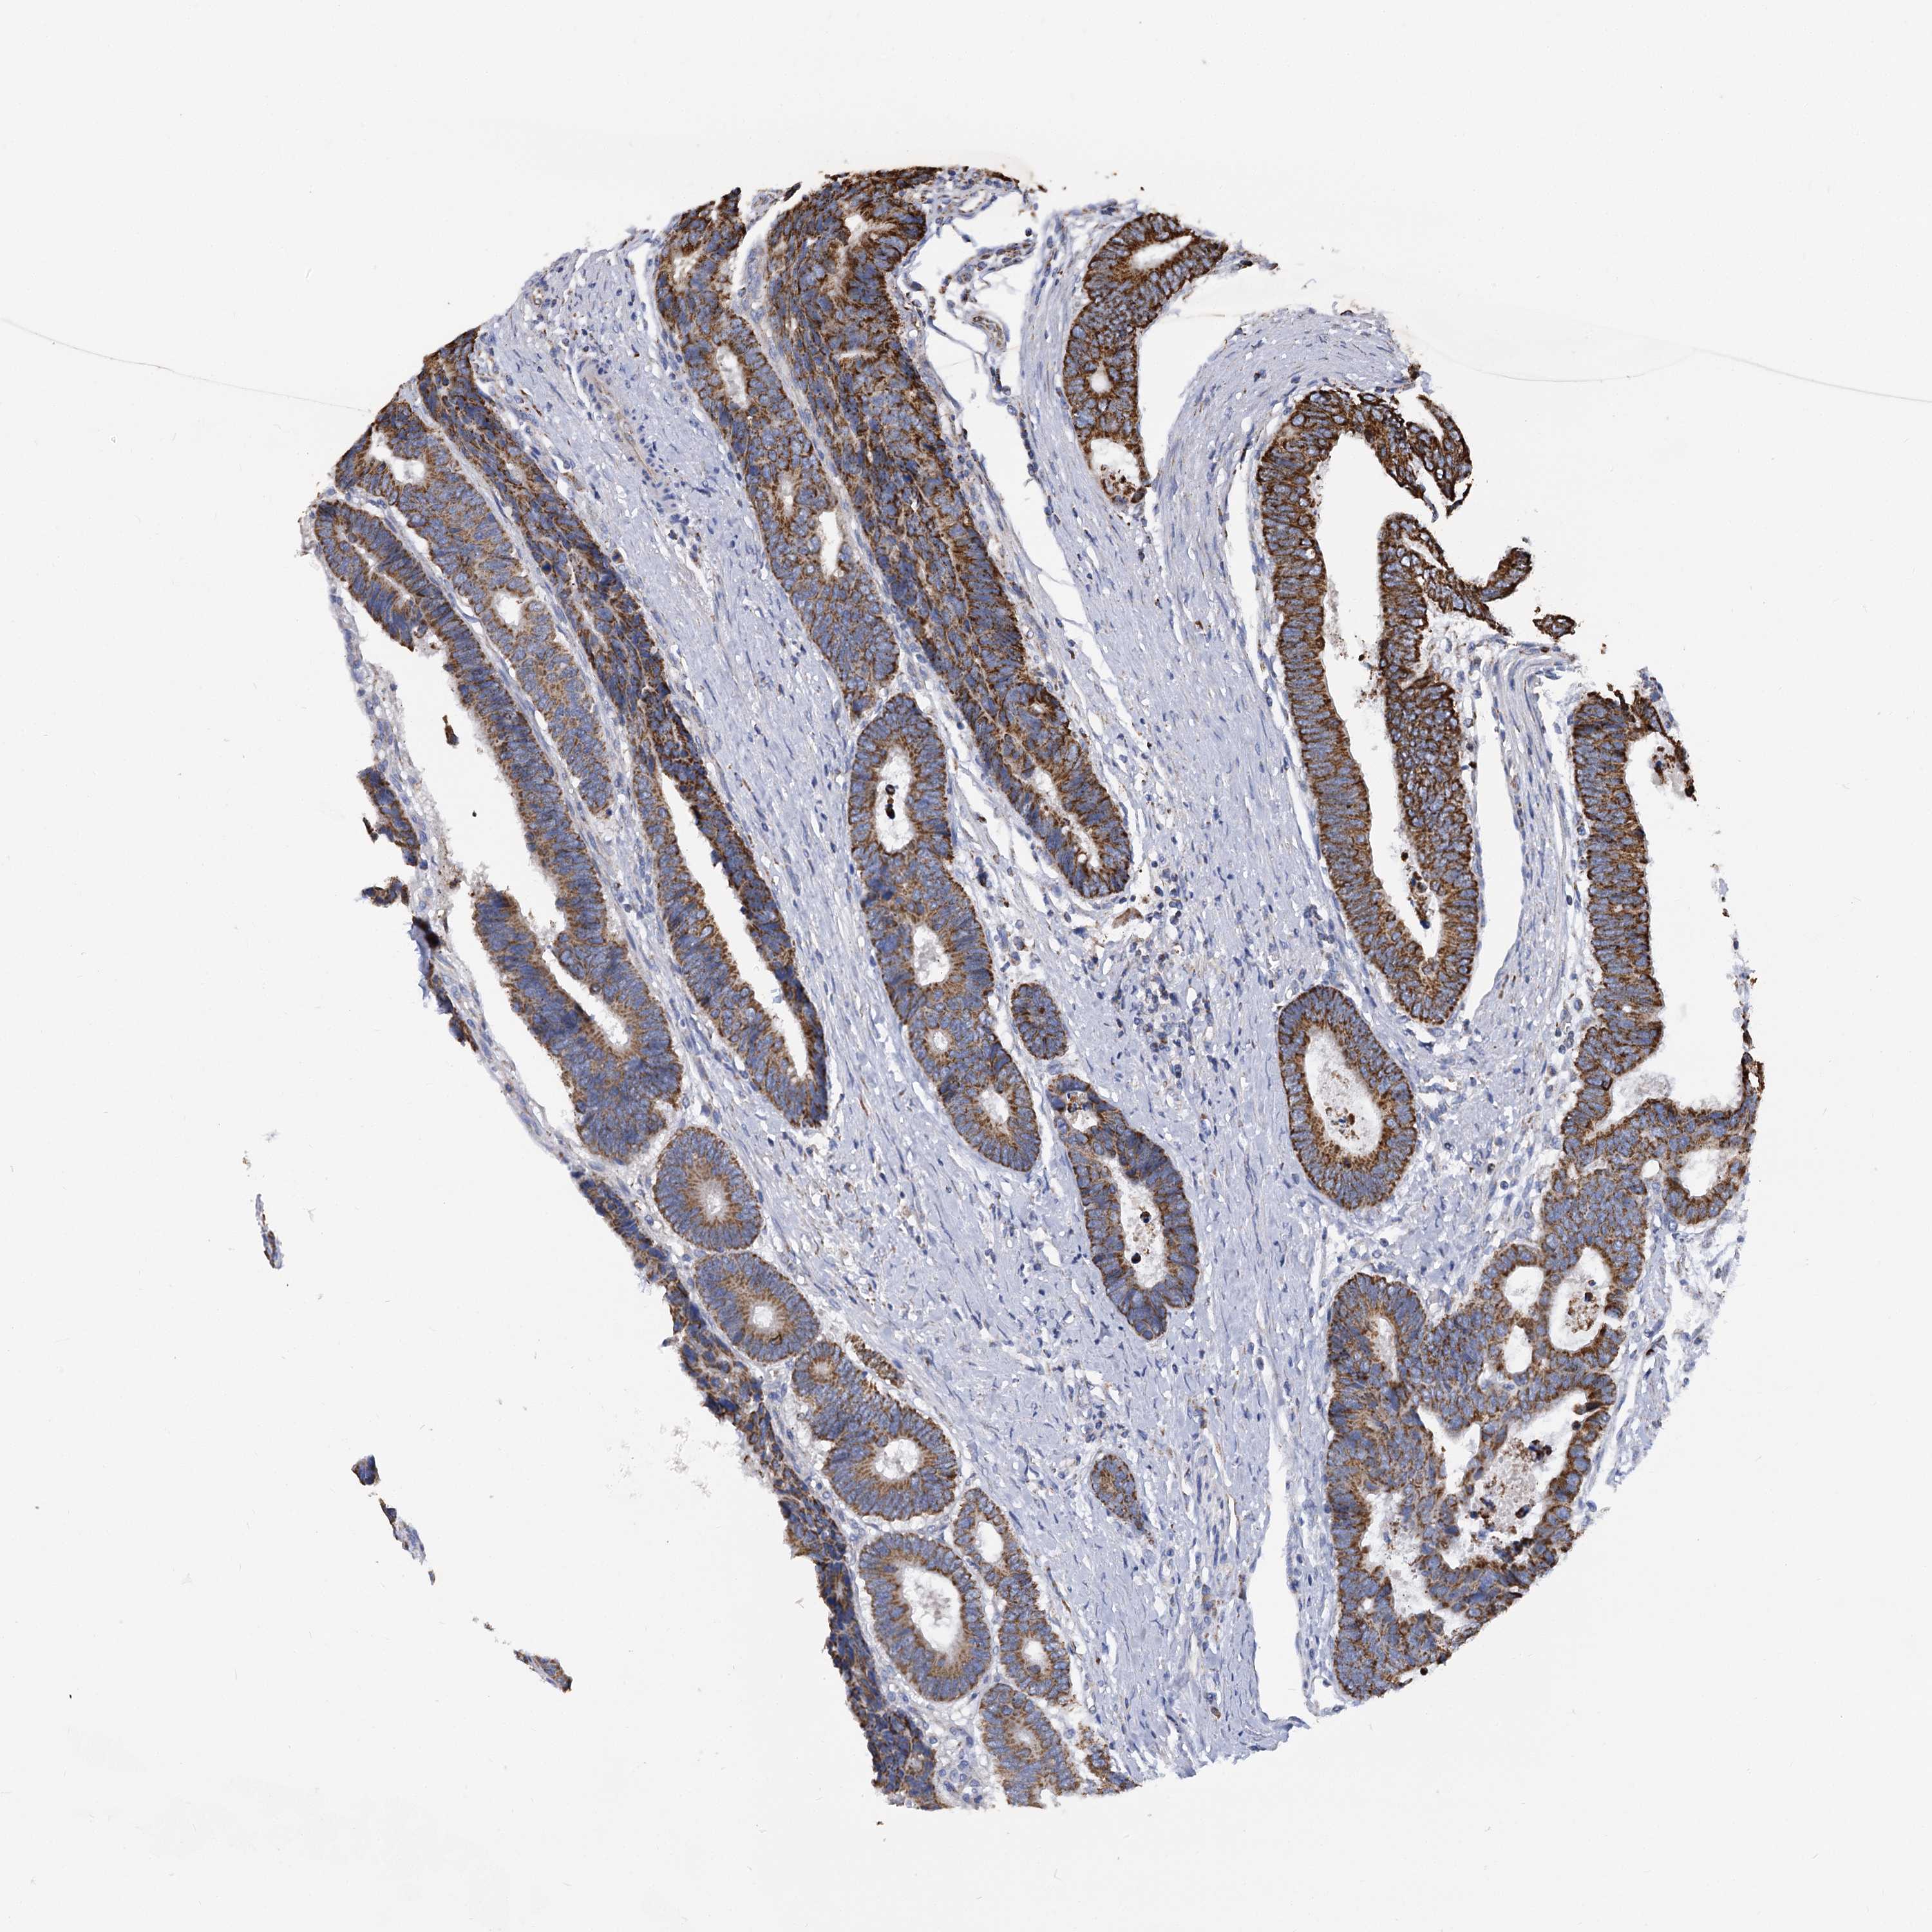

CANCER COLORECTAL CANCER Show tissue menu

Colorectal cancer

Human cancer

Colon adenocarcinoma